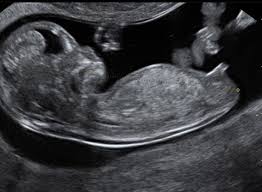

Usia Kandungan Obstetrik Dan Sebenar Menentukan Umur Gestasi Oleh Ultrasound

Hamil 4 bulan = 17minggu 1 hari. Saya puan melakukan pemeriksaan dulu, bagi menentukan puan hamil atau tidak. Usia kandungan adalah masa antara tarikh konsepsi dan kelahiran, atau berapa lama seseorang hamil dalam beberapa minggu. Pangan merupakan kebutuhan dasar manusia yang terpenting disamping papan, sandang, pendidikan, kesehatan. Akhir sekali, yang terbaru, pada tahun 1999, valley et al. Hamil 6 bulan = 24 minggu 5 hari. Berat badan bayi pramatang selalunya antara 500 gm untuk usia kandungan 22 minggu hingga 1000 gm untuk 28 minggu dan 1500 gm untuk 32 minggu dan 2.5 kg untuk 37 minggu. Malaysian journal of learning and instruction: